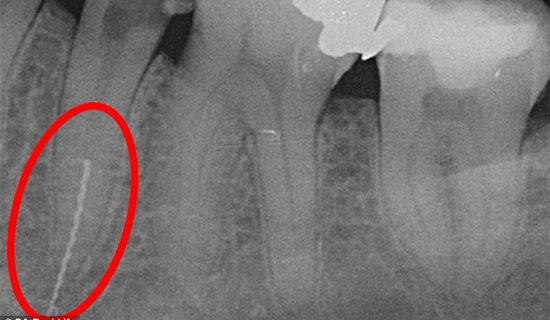

| Phim chụp X Quang cho thấy mũi khoan bị gãy, kẹt sâu trong xương hàm của Alison. |

Tuy nhiên, mũi khoan mắc quá sâu gần phía xương hàm của Alison. Do đó, tất cả những gì nha sĩ có thể làm là phun đầy lại lỗ và đưa cô về nhà.

Alison đã tham khảo ý kiến của các chuyên gia, nhưng không ai dám mạo hiểm lấy nó ra vì rất gần các dây thần kinh, rủi ro quá lớn, có thể làm mất cảm giác xương ở mặt. Trong khi đó, nếu để mũi khoan trong răng quá lâu, nó có thể gây độc cho răng. Cô hy vọng bằng cách nhổ răng, các nha sĩ có thể tiếp cận và loại bỏ mũi khoan. Hiện nay, cô đã được trám răng tạm thời trước khi được thay thế chiếc mới.